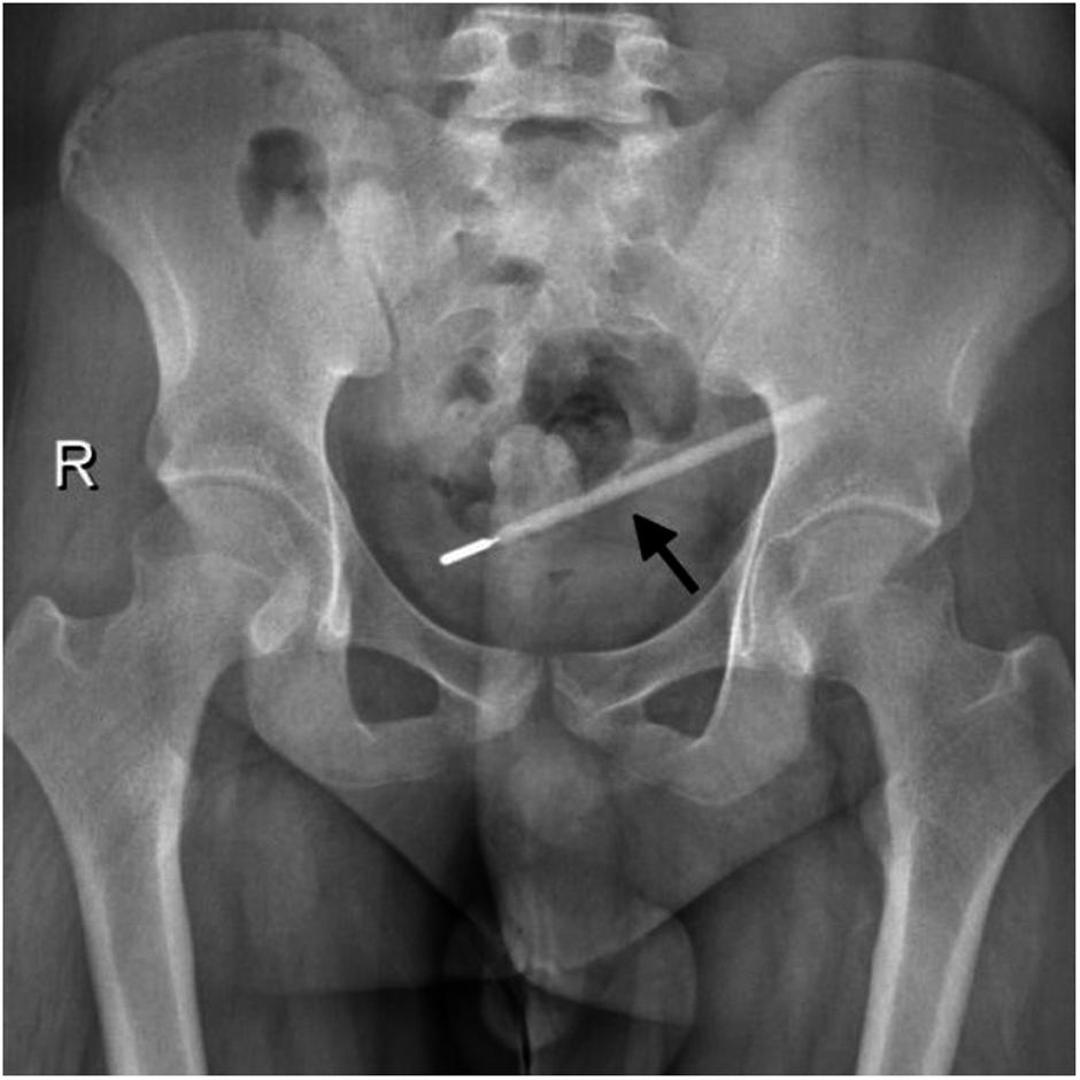

Rutinski posjet bolnici zbog bolova u trbuhu pretvorio se u nevjerojatno otkriće za tridesetdvogodišnjeg muškarca iz kineskog grada Wenzhoua. Pacijent, prezimena Wang, javio se u podružnicu Longgang Prve pridružene bolnice Medicinskog sveučilišta Wenzhou, žaleći se na jake bolove. Liječnici su ga odmah poslali na pretrage, a snimke su otkrile nešto posve neočekivano - u njegovom dvanaesniku, početnom dijelu tankog crijeva, nalazio se dugačak i oštar strani predmet. Sumnje su se ubrzo potvrdile: bio je to stari živin toplomjer, prenosi PubMed Central.

Stanje je bilo alarmantno. Liječnički tim utvrdio je da vrh toplomjera izravno pritišće stijenku crijeva, stvarajući visoki rizik od perforacije i teškog unutarnjeg krvarenja. Svako odgađanje moglo je biti kobno. Kada su suočili pacijenta s otkrićem, Wang je priznao nevjerojatnu priču koja stoji iza misterioznog predmeta. Ispričao je kako je slučajno progutao toplomjer dok je bio dvanaestogodišnji dječak. U to vrijeme, rekao je, previše se bojao roditeljske reakcije da bi im priznao što se dogodilo.

Iako je sama operacija uklanjanja trajala svega dvadeset minuta, bila je iznimno zahtjevna i osjetljiva. Toplomjer se nalazio u neposrednoj blizini žučnih vodova, što je predstavljalo značajan rizik od oštećenja crijevne stijenke tijekom postupka. Kirurzi su morali postupati s krajnjim oprezom, no zahvat je uspješno završen. Na opće iznenađenje, toplomjer je izvađen potpuno netaknut, premda su oznake za mjerenje temperature na staklu s vremenom potpuno izblijedjele.